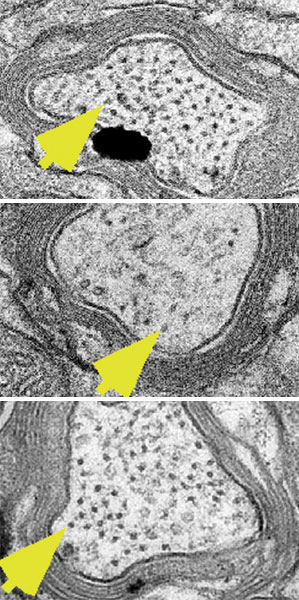

Las traumáticas lesiones cerebrales llevan a la alteración de las estructuras de andamiaje dentro de las neuronas (los puntos negros señalados por las flechas amarillas), como se observa en los cerebros de ratones lesionados que recibieron un placebo (la imagen central).

Un tratamiento experimental ayuda a reestablecer la estructura y función cerebral normal en ratones que han sufrido graves conmociones cerebrales, y podría llevarnos a un fármaco que haría lo mismo en humanos, según una nueva investigación científica.